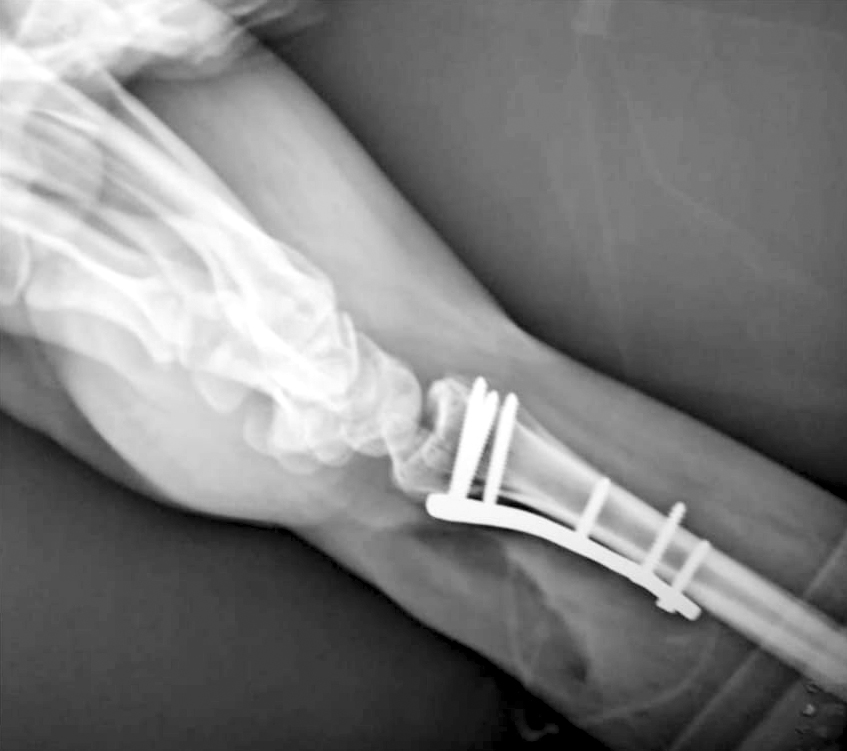

Gracias a la disponibilidad del arco en C, se ha logrado descongestionar centros de mayor complejidad y evitar traslados innecesarios. De esta manera, las intervenciones pueden realizarse localmente, favoreciendo la comodidad de los pacientes y reduciendo tiempos de espera en el sistema de salud.

Este fortalecimiento contribuye directamente a mejorar la capacidad resolutiva del servicio, consolidando un modelo de atención más eficiente y cercano. Asimismo, permite optimizar los recursos disponibles y garantizar una cobertura más amplia a la población que requiere atención especializada.

Los profesionales que hicieron posible estos avances: la Dra. Noelí Zavala, especialista en manos; el Dr. Sergio Trebastoni y el Dr. Enrique Torales, traumatólogos; así como al equipo de anestesiología integrado por el Dr. Gabriel Molinas, la Dra. Johanna Fariña y el Lic. Walter Villalba, junto al plantel de enfermería e instrumentación quirúrgica.